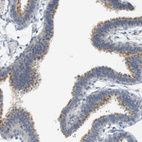

Immunohistochemical staining of human placenta shows strong nuclear positivity in trophoblastic cells.